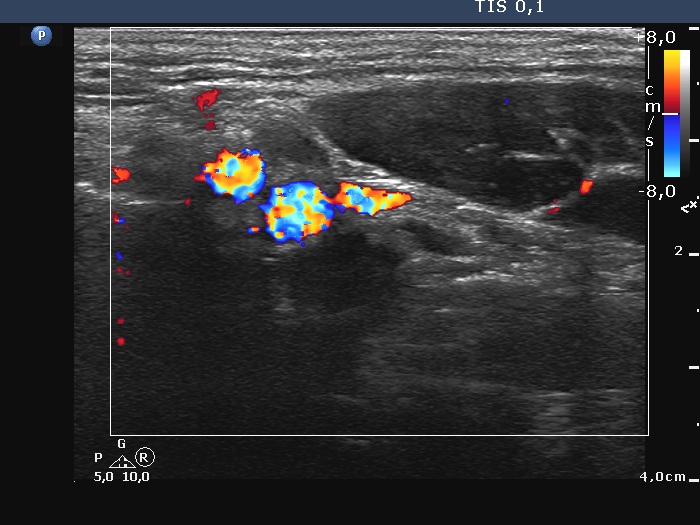

Lymph nodes - case 759 (ultrasonographic picture 6)

Upper part of the left submandibular region, longitudinal scan, color Doppler mode. There are several other, small lymph nodes, one ventral to the vessels, and another one dorsal to the lower two vessels.